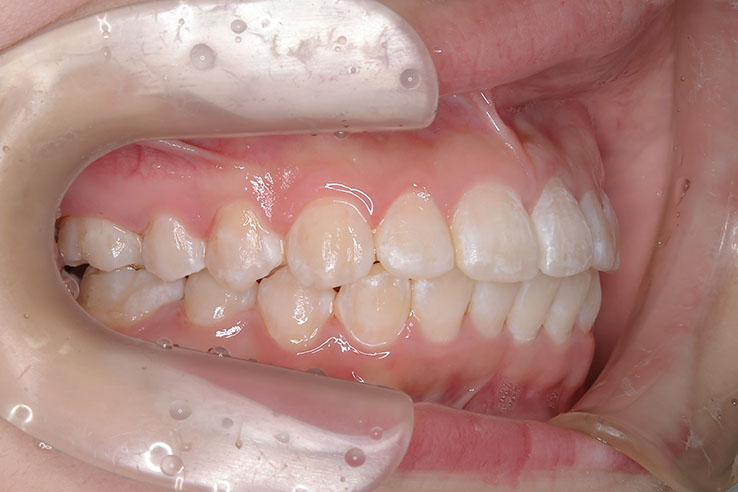

小児矯正での早期治療で、側方拡大による十分なスペース確保をしていたことと、口唇の前突傾向がなかったことから、

平均来院間隔 ほぼ1か月に1度の来院でした。 1か月に1度の来院ですので、治療期間は短く終われました。